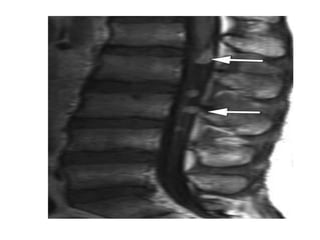

-MRI :

-Typically the tumors demonstrate expansion of the

tectal plate by a solid nodule of tissue

*T1 :

-Iso to slightly hypointense to grey matter

*T2 :

-Hyperintense to grey matter

*T1+C :

-Usually no enhancement

-Higher grade tumors tend to be larger and tend to

enhance more vividly

T1

T2 FLAIR shows a tectal mass leading to obliteration of the

cerebral aqueduct

T1+C shows a slightly hypointense tectal mass which does not

enhance , the mass obstructs the aqueduct and is stable over

8 years